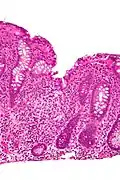

Cryptitis. H&E stain.